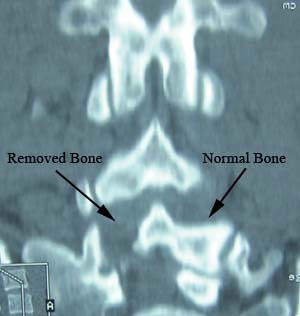

The spine model shown is exactly reconstructed from the CT scan shown below, after a Florida surgeon performed an operation drilling out and removing completely the wall of bone from the left side of the spine in this spot. The upper joint and surface of the joint was also completely removed.

This operation has created permanent and un-necessary damage to what was normal and healthy bone and joint. The patient will never heal or recover from this surgical trauma. Joint cannot re-create itself.

There was nothing wrong with the bone or joint before the surgery. The patient had only a herniated disc problem, which could have been treated without trauma to the normal parts of the spine.